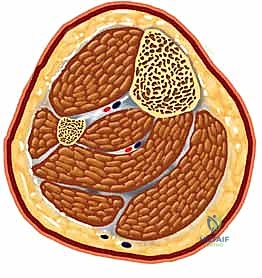

تُعتبر كسور عظم الساق (الظنبوب - Tibia) من أكثر إصابات العظام الطويلة شيوعًا وتعقيدًا في ممارسة جراحة العظام (Orthopedic Surgery) على مستوى العالم. يمثل عظم الساق الدعامة الأساسية التي تحمل الغالبية العظمى من وزن الجسم، وتنقل القوى الحركية والميكانيكية من الركبة إلى الكاحل والقدم أثناء المشي والجري والوقوف.

نظرًا لموقعه التشريحي السطحي جداً (حيث يقع تحت الجلد مباشرة في الجزء الأمامي من الساق دون غطاء عضلي كثيف يحميه)، فإنه يكون عرضة بشكل كبير للإصابات المباشرة وغير المباشرة. هذه الهشاشة التشريحية تجعل كسور الساق غالباً مصحوبة بإصابات في الأنسجة الرخوة المحيطة (الجلد، الأوعية الدموية، والأعصاب)، مما يزيد من تعقيد الحالة ويستوجب تدخلاً طبياً عالي الاحترافية.